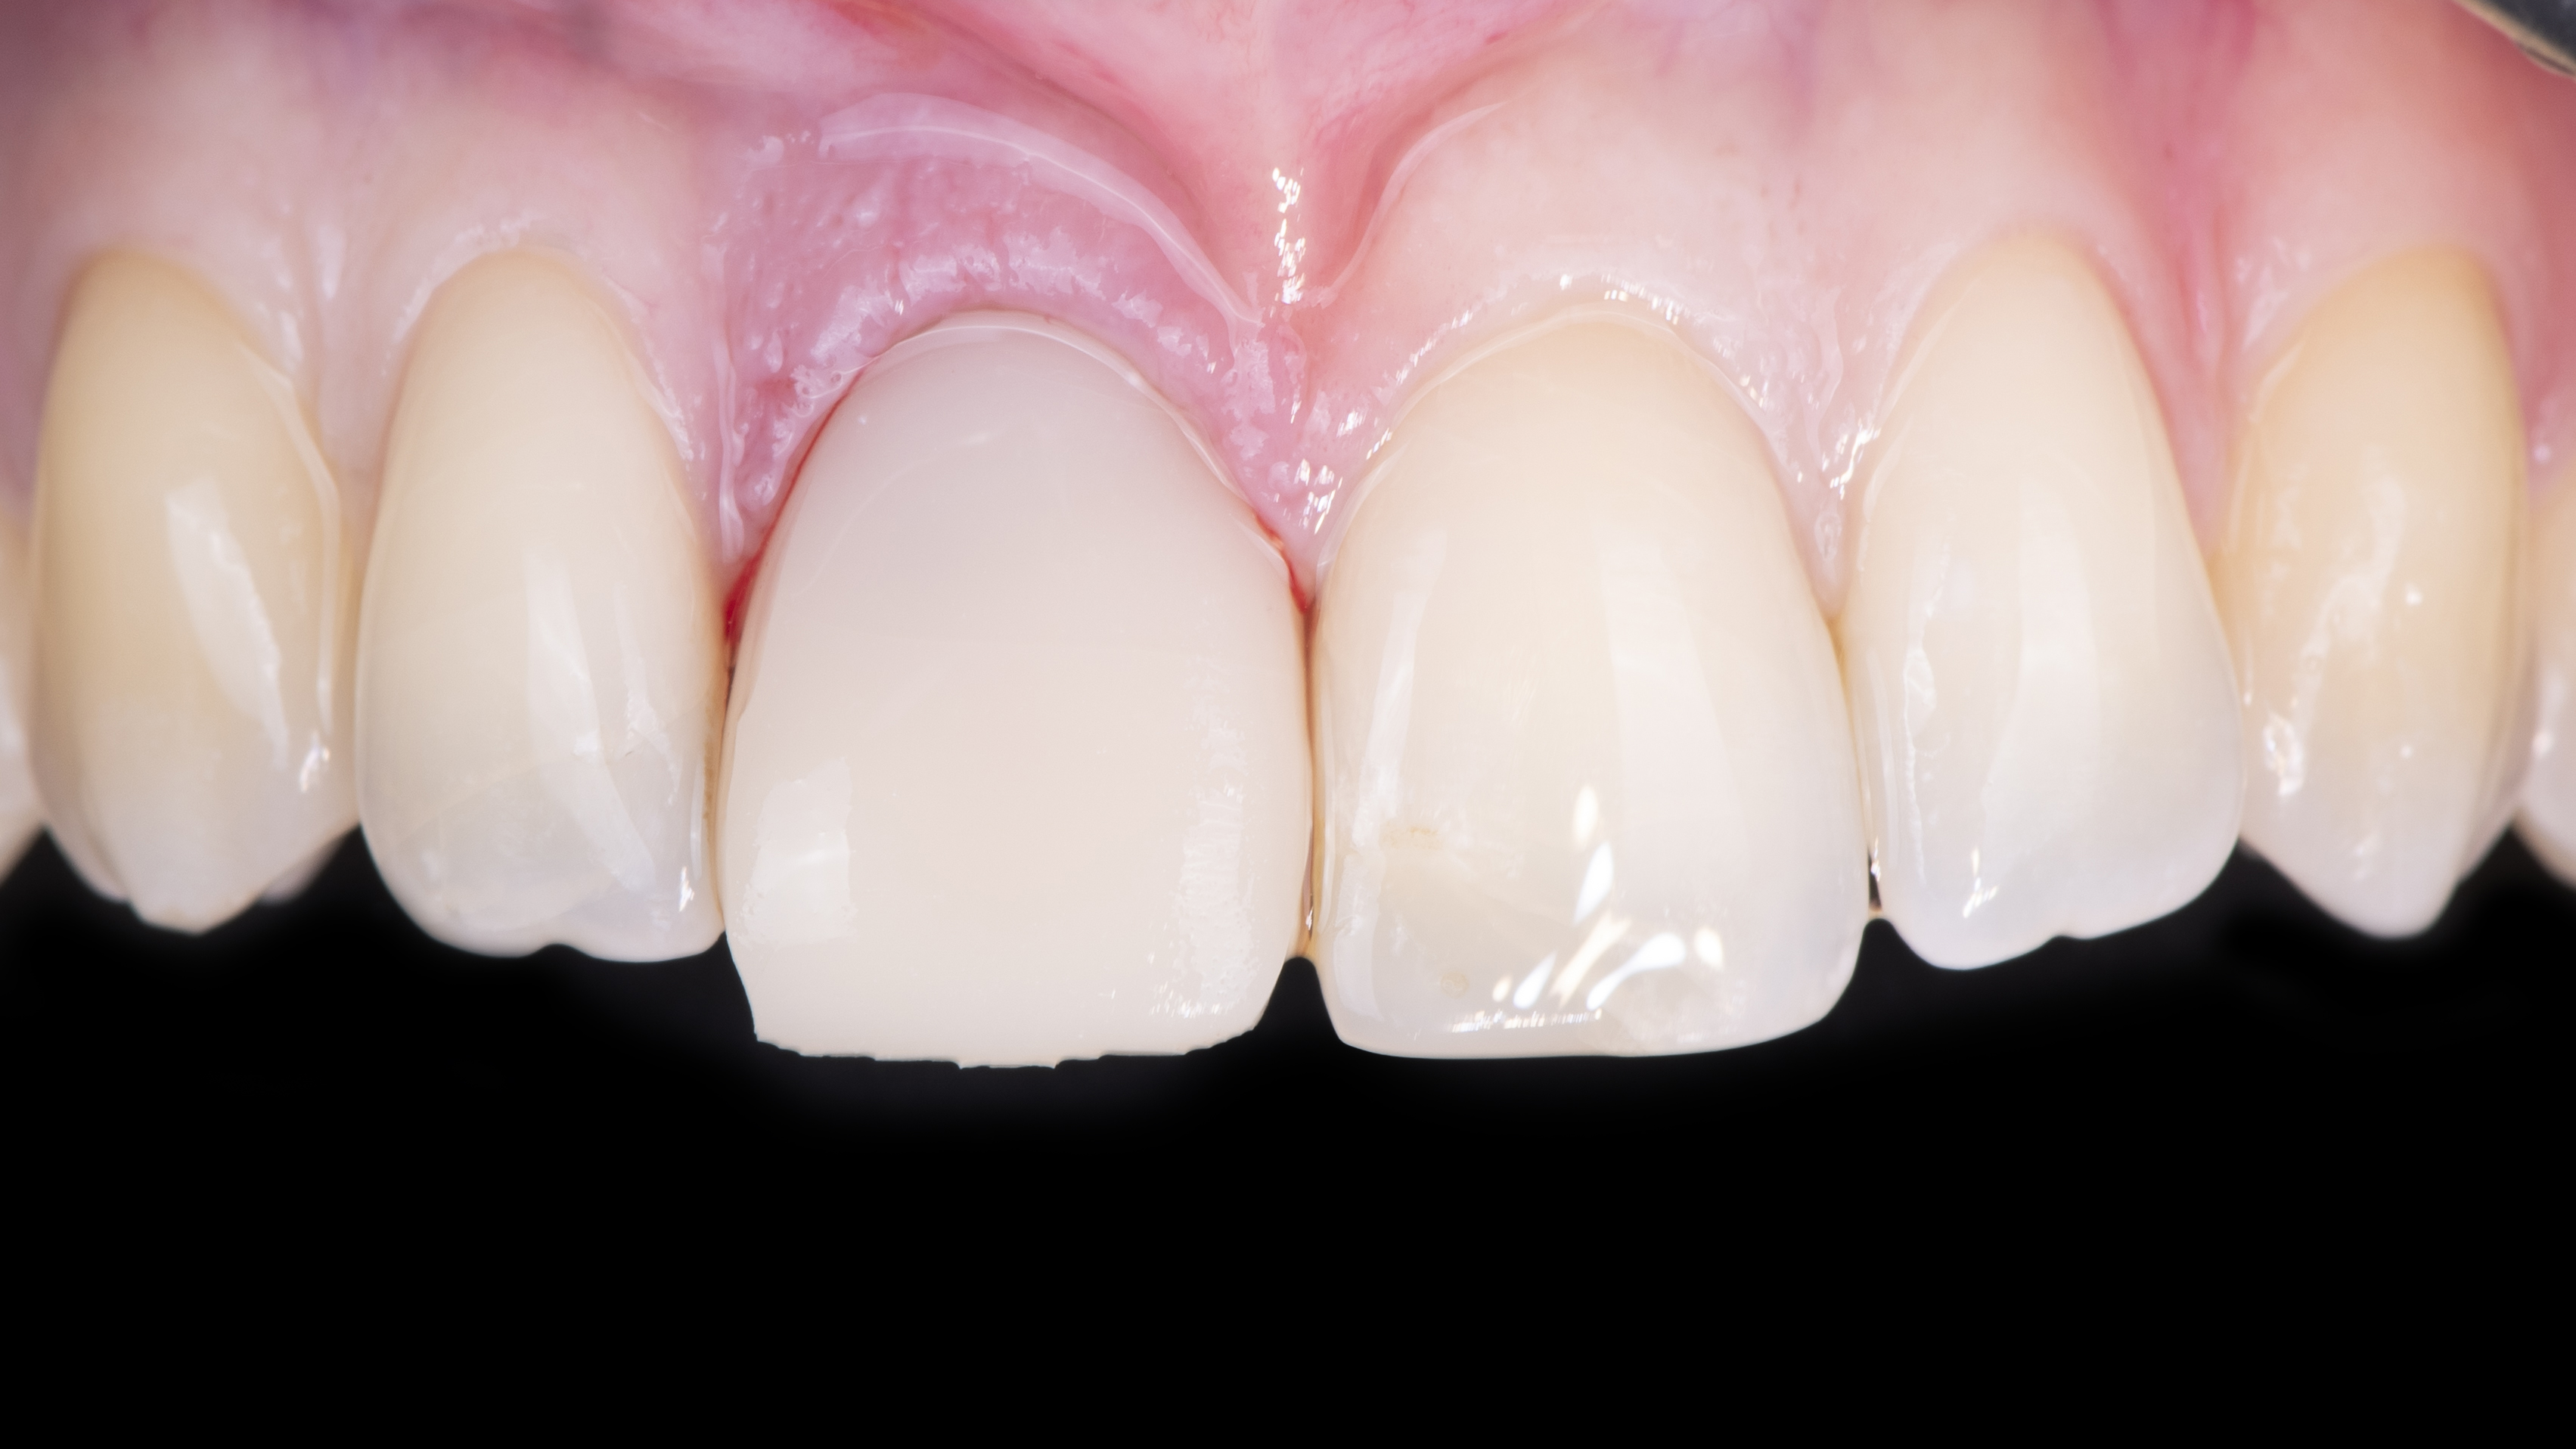

Nous constatons que la cicatrisation est alors optimale et que la prothèse d’usage s’intègre parfaitement à son environnement (Photo 20).

Intégration des réhabilitations au niveau du sourire de la patiente (Photo 26).